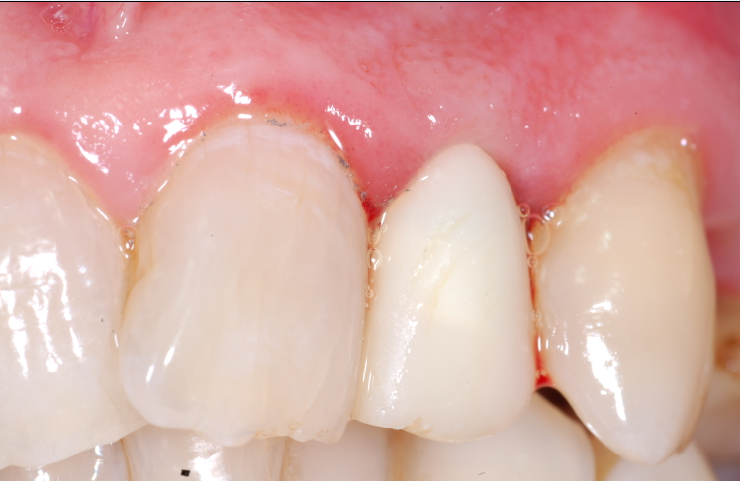

Lo scopo del presente lavoro quello di dimostrare i reali vantaggi che una tecnica delicata, come quella post-estrattiva offre nel riabilitare protesicamente un settore ad alta rilevanza estetica. Il paziente in esame presentava una frattura coronale del 22 devitalizzato, con lesione granulomatosa peri-apicale. Su richiesta del paziente veniva applicata una corona provvisoria e programmato per un impianto post-estrattivo. Le condizioni cliniche del paziente erano buone per cui si procedeva alla pianificazione del caso. Pianificazione che prevedeva, lestrazione del 22 con asportazione del granuloma peri-apicale, disinfezione, cruentazione dellalveolo, ed applicazione di un impianto Nobel-Direct (3.5 x 13 mm). La valutazione intra-operatoria dellaltezza alveolare, della distanza crestale vestibolo-palatale e mesio-distale, facevano propendere per linserimento di un impianto Nobel-Direct della dimensione 4.3 x 13 mm senza fresatura alveolare, ma semplicemente avvitandolo nellalveolo e raggiungendo una forza di serraggio > di 45 N. Preparare il sito implantare per una maggiore profondit avrebbe creato problemi per lasse implantare determinando una eccessiva vestibolarizzazione del moncone. Si procedeva allapplicazione ed alladattamento del provvisorio dopo una piccola correzione del moncone. Nota importante da sottolineare il perfetto adattamento del provvisorio, non solo al pilastro implantare ma anche alla mucosa gengivale, dove soprattutto nellimplantologia post-estrattiva lemergenza dellimpianto non sar mai perfettamente aderente n alla cresta alveolare, quasi sempre a sezione ovalare, n alla mucosa gengivale. Il sigillo mucosale garantisce la formazione ed il mantenimento di quel coagulo ematico che andr a colmare il gap tra osso, impianto e corona, impedendo laccumulo di residui alimentari e di placca, che minerebbero sicuramente questa zona critica. Si comprende pertanto che il provvisorio non deve invadere uno spazio che non gli compete, ma deve occupare sicuramente quello spazio che prima competeva alla corona riproducendo perfettamente gli stessi rapporti con i tessuti limitrofi. Al paziente veniva consigliata una copertura antibiotica (Amoxicillina cpr 1 gr/12 ore x 5 gg,; Efferalgan cpr 1 cpr alloccorrenza; Dentosan collutorio 0,20% - 3-4 sciacqui al die x 10 gg) evitare sovraccarichi masticatori, di poter incidere ma di non strappare i cibi. Il paziente veniva controllato dopo 7 giorni, ad 1 mese ed al terzo mese, periodo questultimo in cui si procedeva ad un controllo rx endorale alla preparazione del pilastro con ribasatura del provvisorio. Dopo circa 7 giorni si rilevavano le impronte di precisione e quindi si finalizzava il lavoro. Possiamo ritenerci soddisfatti del risultato finale, sia clinico, che radiografico ed estetico, considerando le difficolt presentatesi durante lintervento. Tra queste annoveriamo sicuramente lestrazione del residuo radicolare, devitalizzato, con granuloma peri-apicale e lesiguit della corticale vestibolare, che doveva essere assolutamente conservata. Il risultato estetico finale, tessuti molli e corona dentaria, sicuramente soddisfacente, e deriva da una cura minuziosa dei particolari chirurgici e protesici, sempre nel rispetto massimo dei tessuti.

Il paziente in esame stato sottoposto ad estrazione del residuo radicolare del 22 con asportazione di granuloma peri-apicale ed inserimento contestuale di una fixture monofasica (Nobeldirect) con protesi fissa provvisoria. Il caso stato completato con protesi fissa oro-ceramica dopo tre mesi dall'intervento.